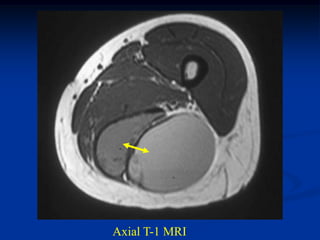

The desmoid tumor does not calcify but is radiodense on ordinary

radiographs and can be easily identified on a soft tissue window CT

scan. The MRI is the best imaging study for this tumor and will be

low signal on the T-1 weighted image but only intermediate high

signal on the T-2 because of the low water content in this tumor

which helps separate it from malignant MFH and fibrosarcoma.

CLASSIC   Case #250.1

Axial T-1 MRI

50 year male with desmoid tumor thigh